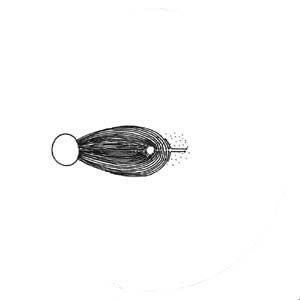

Výpadky nervových vláken na sítnici a graficky na perimetru podle Minclera

Lokalizovaný výpadek nervových vláken byl popsán poprvé teprve roku 1973 Hoytem. Je vějířovitého tvaru, připomínající ocas komety. Vyskytuje se u 20% glaukomů, není však pro glaukom specifický (drůzy, chorioretinální jizvy, dlouho trvající edém disku, pozánětlivá atrofie). Není u zdravých očí.

Korelace lokálního výpadku nervových vláken se změnami zorného pole dle Minclera

Když exkavace zasahuje až okraji terče dochází k poškození vláken, která vedou až do temporální části sítnice k tělům gangliových buněk, uloženým v sousedství horizontálního švu. Poškození těchto buněk a jejich axonů se projeví nasálním skokem s arkuátním Bjerumovým skotomem.

Pokud exkavace nedosahuje k samému okraji terče (miskovité exkavace), svědčí to pro poškození vláken z povrchnější vrstvy, které směřují k gangliovým buňkám uloženým paracentrálně – periferně od makulopapilárního svazečku. Poškození těchto buněk a jejich axonů se projeví paracentrálními skotomy.